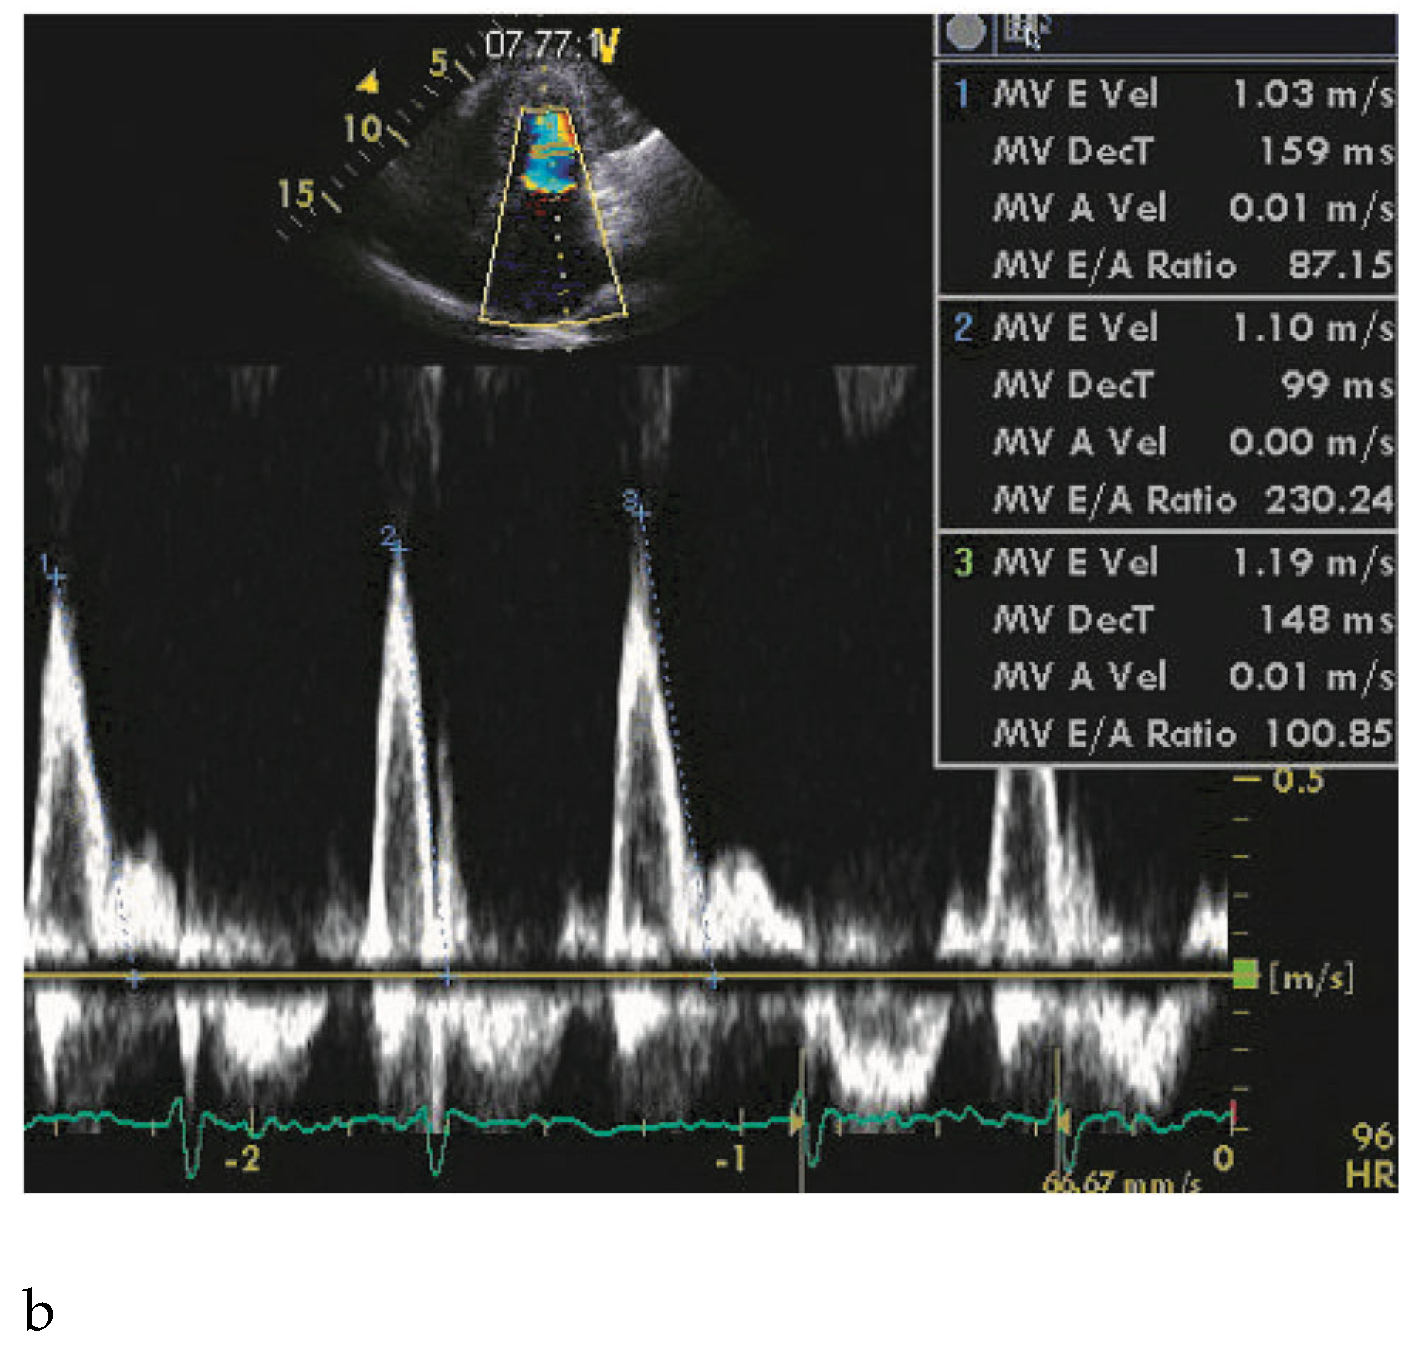

A 66-year-old woman with a family history of hypertrophic cardiomyopathy (HCM) presented with severeprogressive exertional dyspnoea. She had recently complained of palpitations corresponding to atrial fibrillation on the ECG. A transthoracic echocardiogram (TTE) showed nonobstructive, slightly asymmetrical left ventricular hypertrophy (septum and posterior wall thickness respectively measured at 20 and 15 mm). Left ventricular (LV) cavity and ejection fraction (70%) were normal, but both atria were enlarged (Figure 1A). Diastolic function assessment was suggestive of restrictive physiology (Figure 1B). The patient did not improve despite successful cardioversion and intensive medical therapy with maximally-tolerated doses of beta-blockers and verapamil. She was then referred to the catheterisation laboratory to undergo left and right heart catheterisation and coronary angiography after proach) and left heart catheterisations were performed and revealed signs of restrictive physiology without intraventricular dynamic obstruction (Figure 2, Table 1). However, the PA pressure was only mildly elevated and the ventricular diastolic pressure showed a subtle dipplateau pattern (square root sign).

Figure 1. A: Four-chamber view showing a severely dilated left atrium. B: Deceleration time <150 m/sec (in atrial fibrillation), suggestive of a restrictive physiology.